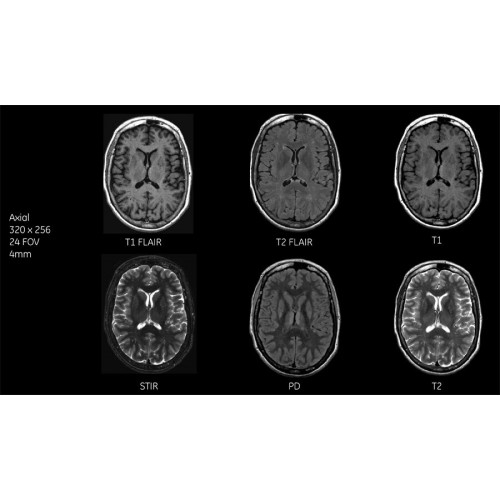

МРТ аппарат GE SIGNA Voyager 1.5T позволяет проводить полный спектр магнитно-резонансных исследований, включая нейровизуализацию, исследования опорно-двигательного аппарата, органов брюшной полости и малого таза, а также специализированные кардиологические программы.

Поддержка современных протоколов

• Неврология и нейрохирургия

• Ортопедия и травматология

• Онкологическая диагностика

• Кардиологические исследования

• Обследования органов брюшной полости и малого таза